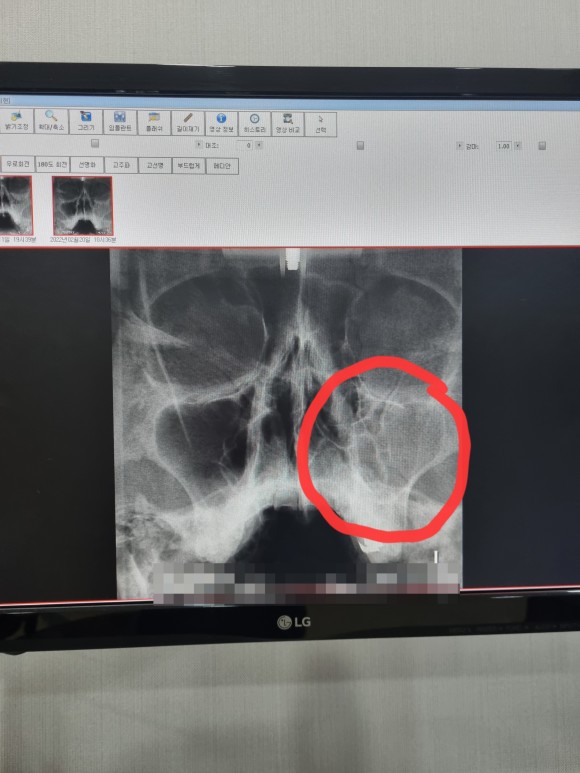

부비강염

잘 구별하기는 힘들겠지만 오른쪽을 보시면

절반이나 염증이 없어진 것을 확인할 수 있다.

정말 다행이야

내시경으로 콧속을 들여다봤을 때도 맑은 콧물이 보인다고 했다.